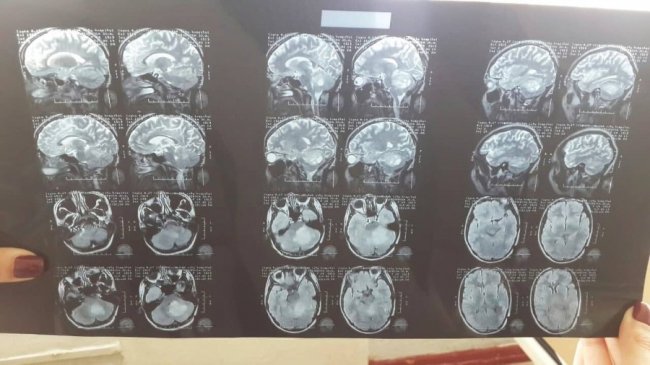

24-річна дівчина скаржилася на нудоту, блювоту, запаморочення, неможливість самостійно ходити. Невропатологом була скерована в Луцьку міську клінічну лікарню на обстеження, де, за результатами МРТ, у неї виявили пухлину. Пацієнтку перевели в нейрохірургічне відділення, однак прооперувати Юлію в умовах цього медзакладу можливості немає через відсутність спеціального мікроскопа.

Нейрохірурги з київської лікарні «Феофанія» очікують пацієнтку на консультацію якнайшвидше і наголошують, що операція необхідна в найшвидші строки, адже пухлина перекриває відтік ліквора зі шлуночка в спинномозковий канал.